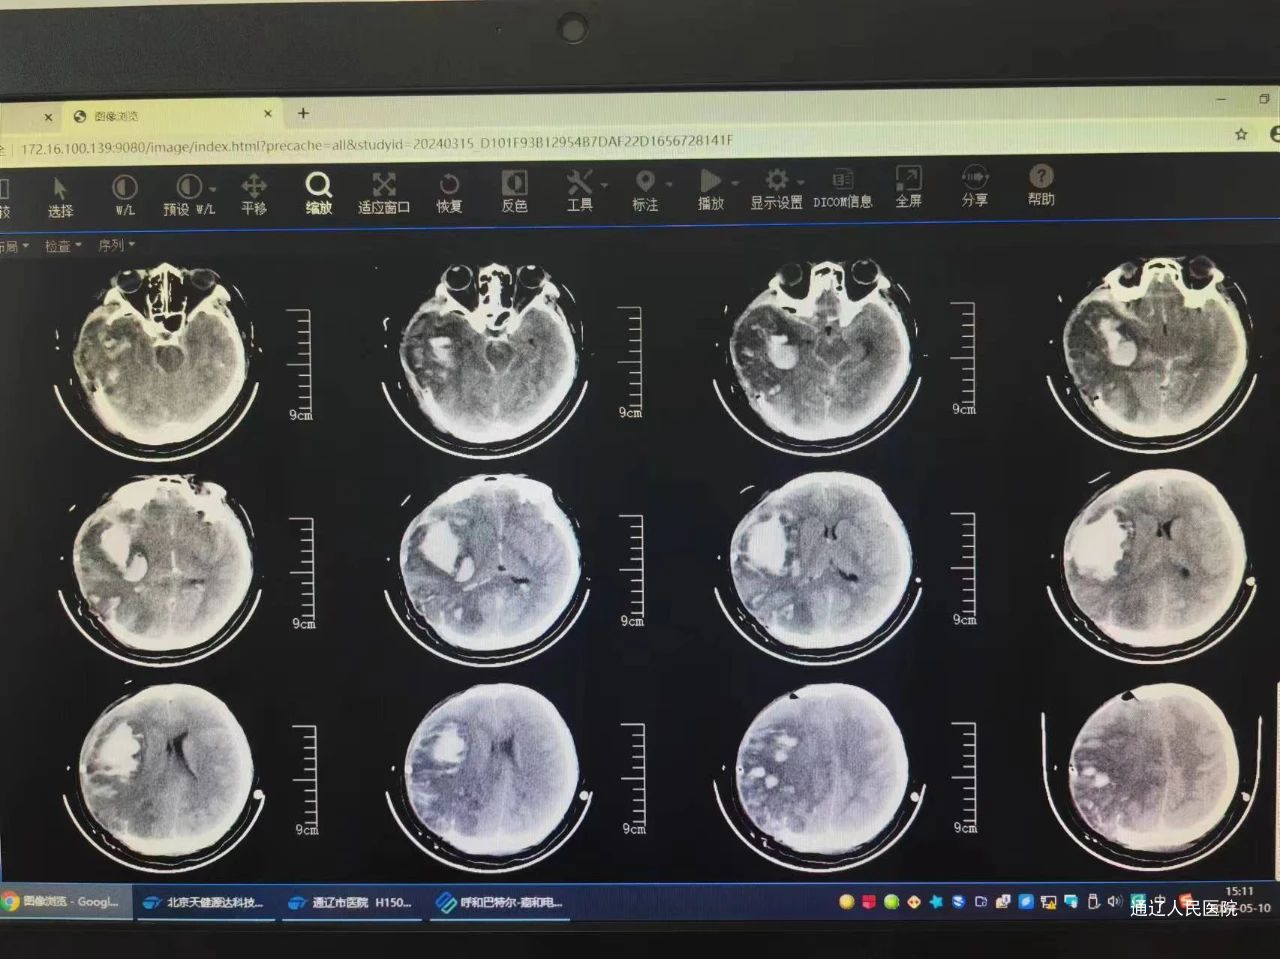

第二次手术前

第三次手术前